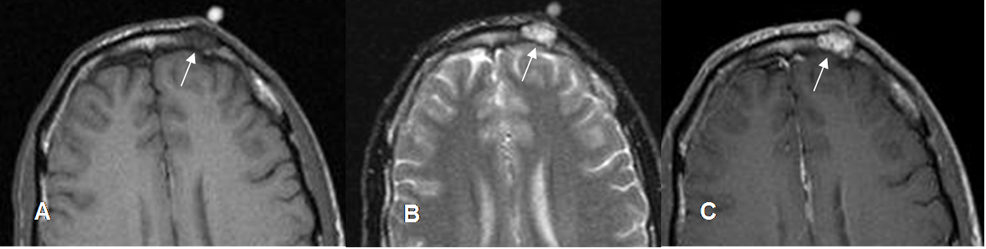

Fig 132. Granuloma eosinófilo.

A: RM axial en T1, B: RM axial en T2 y C: RM axial en T1 con contraste. Lesión frontal izquierda hipointensa en T1, hiperintensa en T2 y que realza con el contraste, por granuloma eosinófilo.